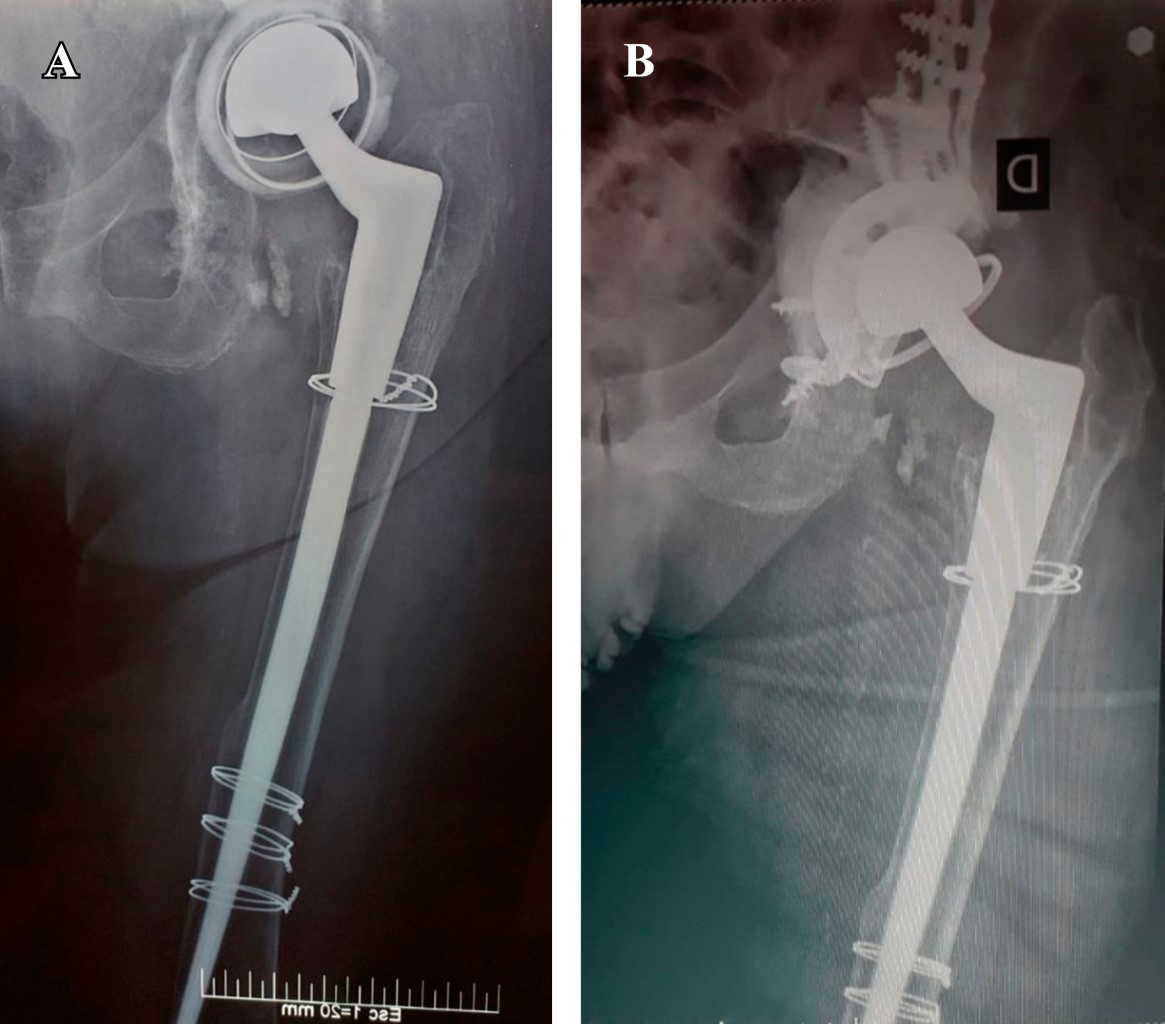

La reimplantación de los componentes cementados y no cementados se llevó a cabo en una y dos etapas, respectivamente (como se resume en la Tabla 2). Se conservaron tanto el componente acetabular como el femoral (Figuras 1 y 2).

Figura 2